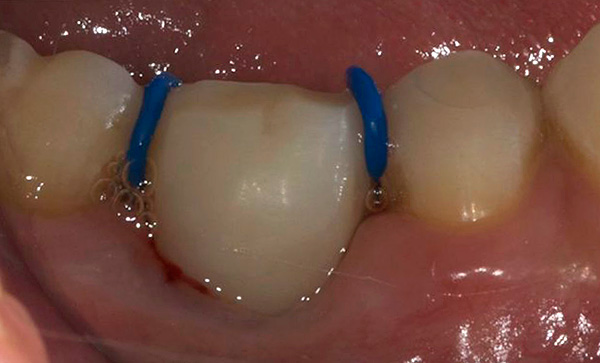

Para facilitar a erupção dos dentes de leite, os ortodontistas usam anéis de separação especiais, que são instalados no espaço entre os dentes existentes. Assim, a pressão exercida sobre o dente causa uma erupção completa. Este método pode ser usado quando a coroa estiver na metade do osso.

- O impacto dos molares permanentes é um fenômeno em que um molar permanente não pode entrar em erupção, pois é bloqueado por dentes temporários ou permanentes adjacentes. Você pode tentar ajudar o dente a cortar usando os anéis de separação de borracha mencionados anteriormente ou usando uma ligadura de metal, que o médico coloca no espaço gengival entre os dentes.A pressão exercida dessa maneira contribui para a saída do dente das gengivas (para criar o espaço necessário, um dos dentes que bloqueia o causador deve ser removido);